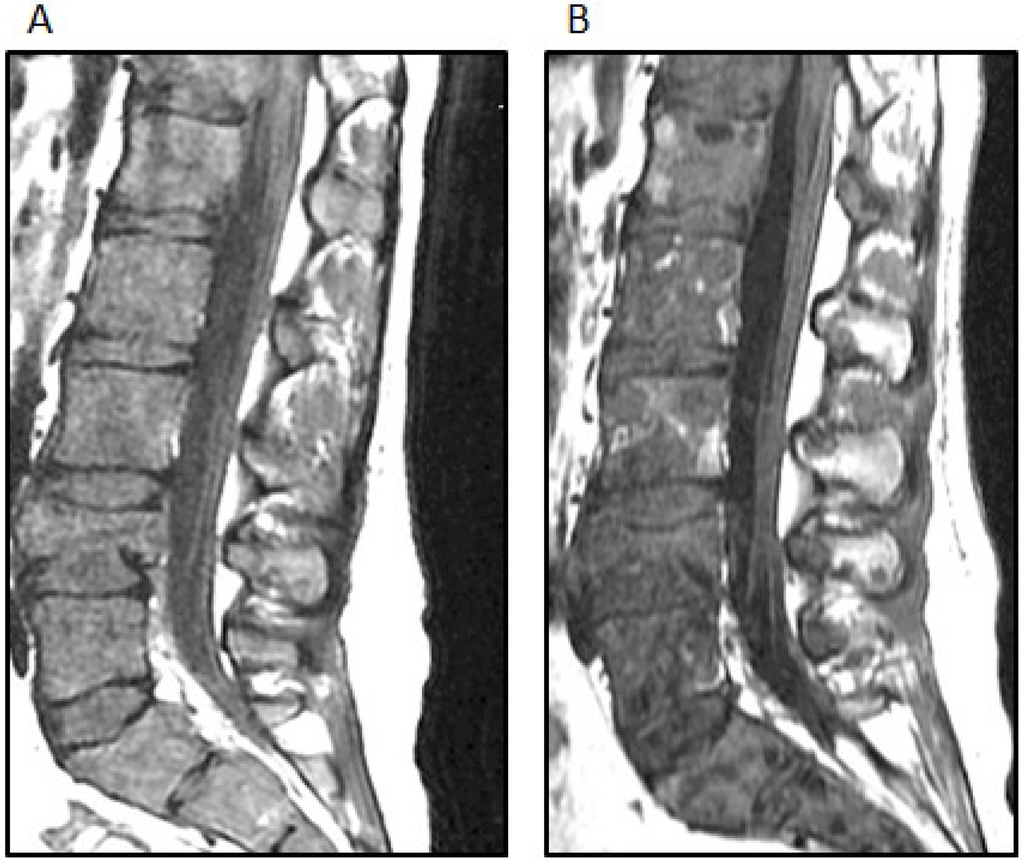

A 12-year-old girl presented with a history of frontal headaches for several weeks after suffering minor head trauma. The initial CT scan without contrast showed no evidence of intracranial bleeding. Because of persistent headaches, however, as well as nausea and vomiting, she underwent another CT scan less than a month later that showed a 6.2 × 3.5 cm right fronto-temporal mass with associated edema and a midline shift. Magnetic resonance imaging (MRI) of the brain with and without intravenous gadolinium was then performed and demonstrated a 5.5 × 2.2 × 5.1 cm, apparently extra-axial mass, largely within the right Sylvian fissure (Figure 1A). The interface of the brain was lobulated and irregular, raising the possibility of the invasion of the brain and subarachnoid space, but no definite intraparenchymal component was recognized. There was vasogenic edema in the subcortical white matter and a 5-mm midline shift towards the left side. Based on imaging, it was felt that the tumor was likely to be a hemangiopericytoma. Physical examination was notable for an intact neurological examination.

The patient underwent a right-sided craniotomy after a successful partial embolization of the tumor the day prior (Figure 1B). A significant portion of the mass was visualized, deep to middle cerebral artery branches shown by intraoperative ultrasound to be coursing through the mass and providing blood supply to the temporal and frontal lobes. The attempted dissection of the tumor off the pial surface also led to devascularization of the underlying brain as the tumor had parasitized the pial vasculature. Therefore, further dissection following superficial excisional biopsy of the mass was not performed for safety reasons. A dural graft was placed. Because of significant brain swelling, the bone flap was not immediately replaced. The temporalis muscle was closed in apposition to the dural graft. Postoperative MR imaging showed that the resection of the anterior and superior aspects of the mass had been accomplished, although the majority of the mass remained (Figure 1C). Microscopic examination revealed a cellular neoplasm with clear or eosinophilic cytoplasm in sheets, small nests and pseudopapillary formations associated with small foci of necrosis (Figure 2A). There were rare mitotic figures. Thin connective tissue bands with blood vessels containing endothelial hyperplasia were frequent. Immunostaining revealed vimentin in all of the tumor cells and scattered tumor cells positive for bcl-2, p53, desmin and factor XIIIa. CD99 and CD34 were negative. The mitotic labeling index using Ki-67 staining was approximately 10%. The initial pathologic diagnosis was hemangiopericytoma.

Figure 1. (A) The post-contrast T1-weighted MRI image shows a predominantly heterogeneously enhancing mass extending into the right Sylvian fissure with probable invasion of the adjacent insular cortex; (B) a select image from the tumor embolization demonstrates a dramatically hypervascular tumor supplied by branches of the right middle meningeal artery that was successfully embolized with polyvinyl alcohol particles; (C) the postoperative T1-weighted MRI image with contrast demonstrates partial resection of the tumor.